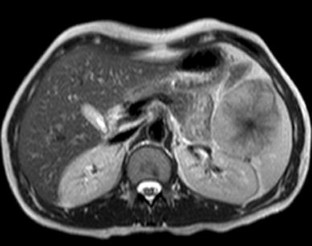

Fig. 4